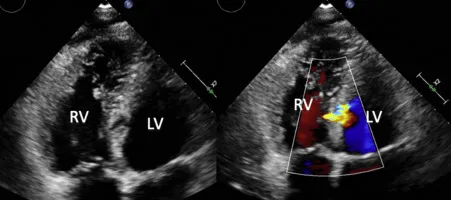

VSD - The Septal Breach

- Timeline: Acute, catastrophic event 3-5 days post-MI.

- Exam: New, loud, harsh holosystolic murmur at the left lower sternal border (LLSB), often with a palpable thrill.

- Pathophysiology: Rupture of the interventricular septum creates a left-to-right shunt, leading to acute RV overload and cardiogenic shock.

⭐ Key Diagnostic Finding: A significant O₂ saturation “step-up” from the right atrium to the right ventricle confirms the diagnosis during catheterization.